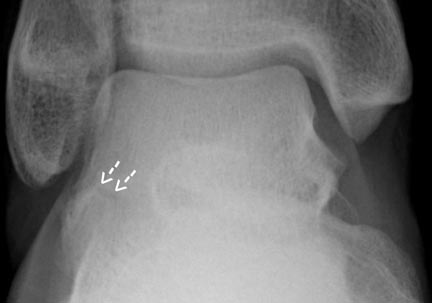

Ankle Fractures